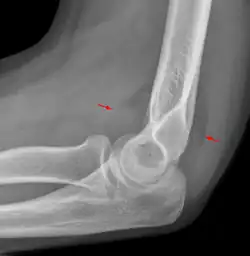

Anterior sail signs as well as posterior fat pad in a child with a supracondylar fracture.

A subtle radial head fracture with associated positive sail sign